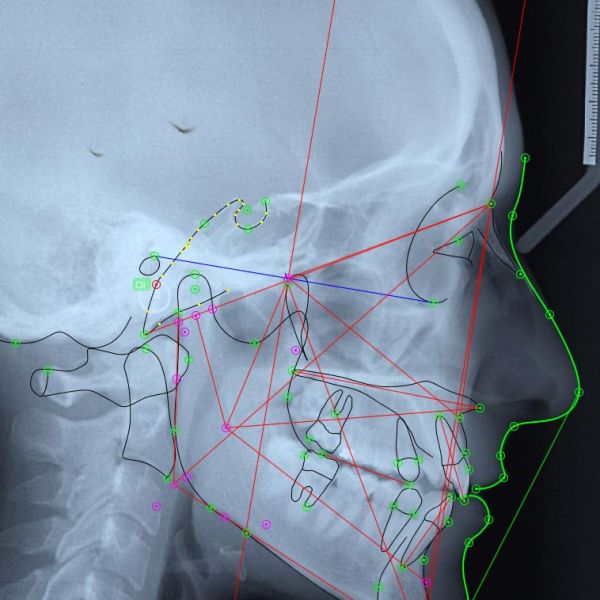

Tracciati Cefalometrici, Dispositivi personalizzati, Splint Chirurgici Ortognatici, Realizzazione di modelli ortodontici, supporto, assistenza, ritiri in laboratorio e consegne

Le nostre Lavorazioni

-